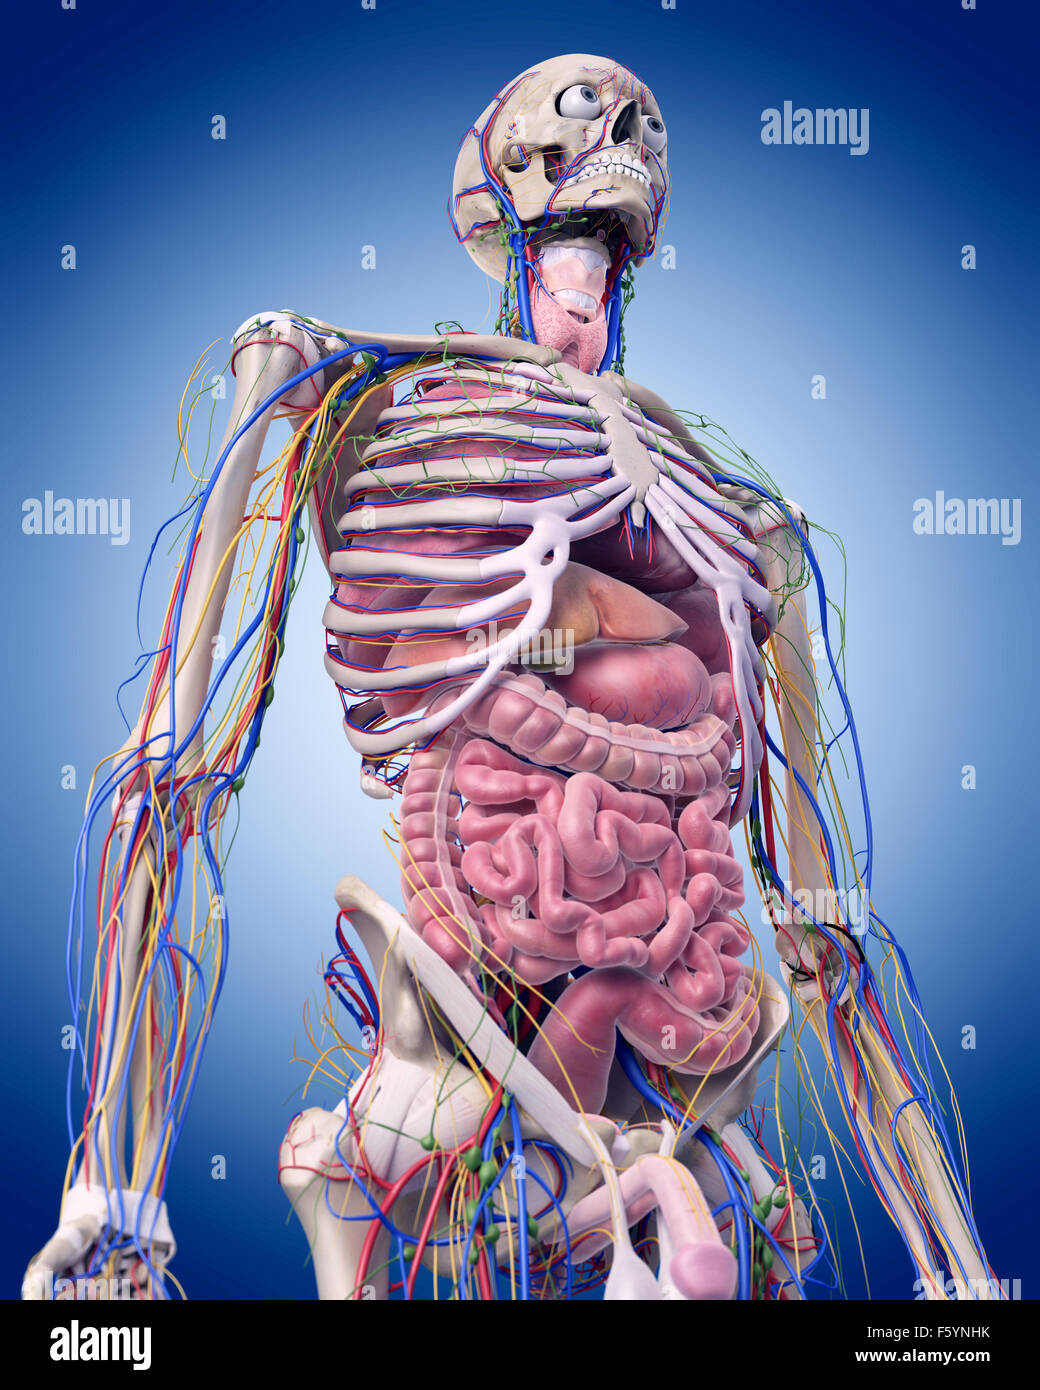

abdomen anatomy model Medically accurate illustration of the abdominal anatomy stock photo

Medically Accurate Illustration Of The Abdominal Anatomy Stock Photo

www.alamy.comabdominal medically accurate

www.alamy.comabdominal medically accurate